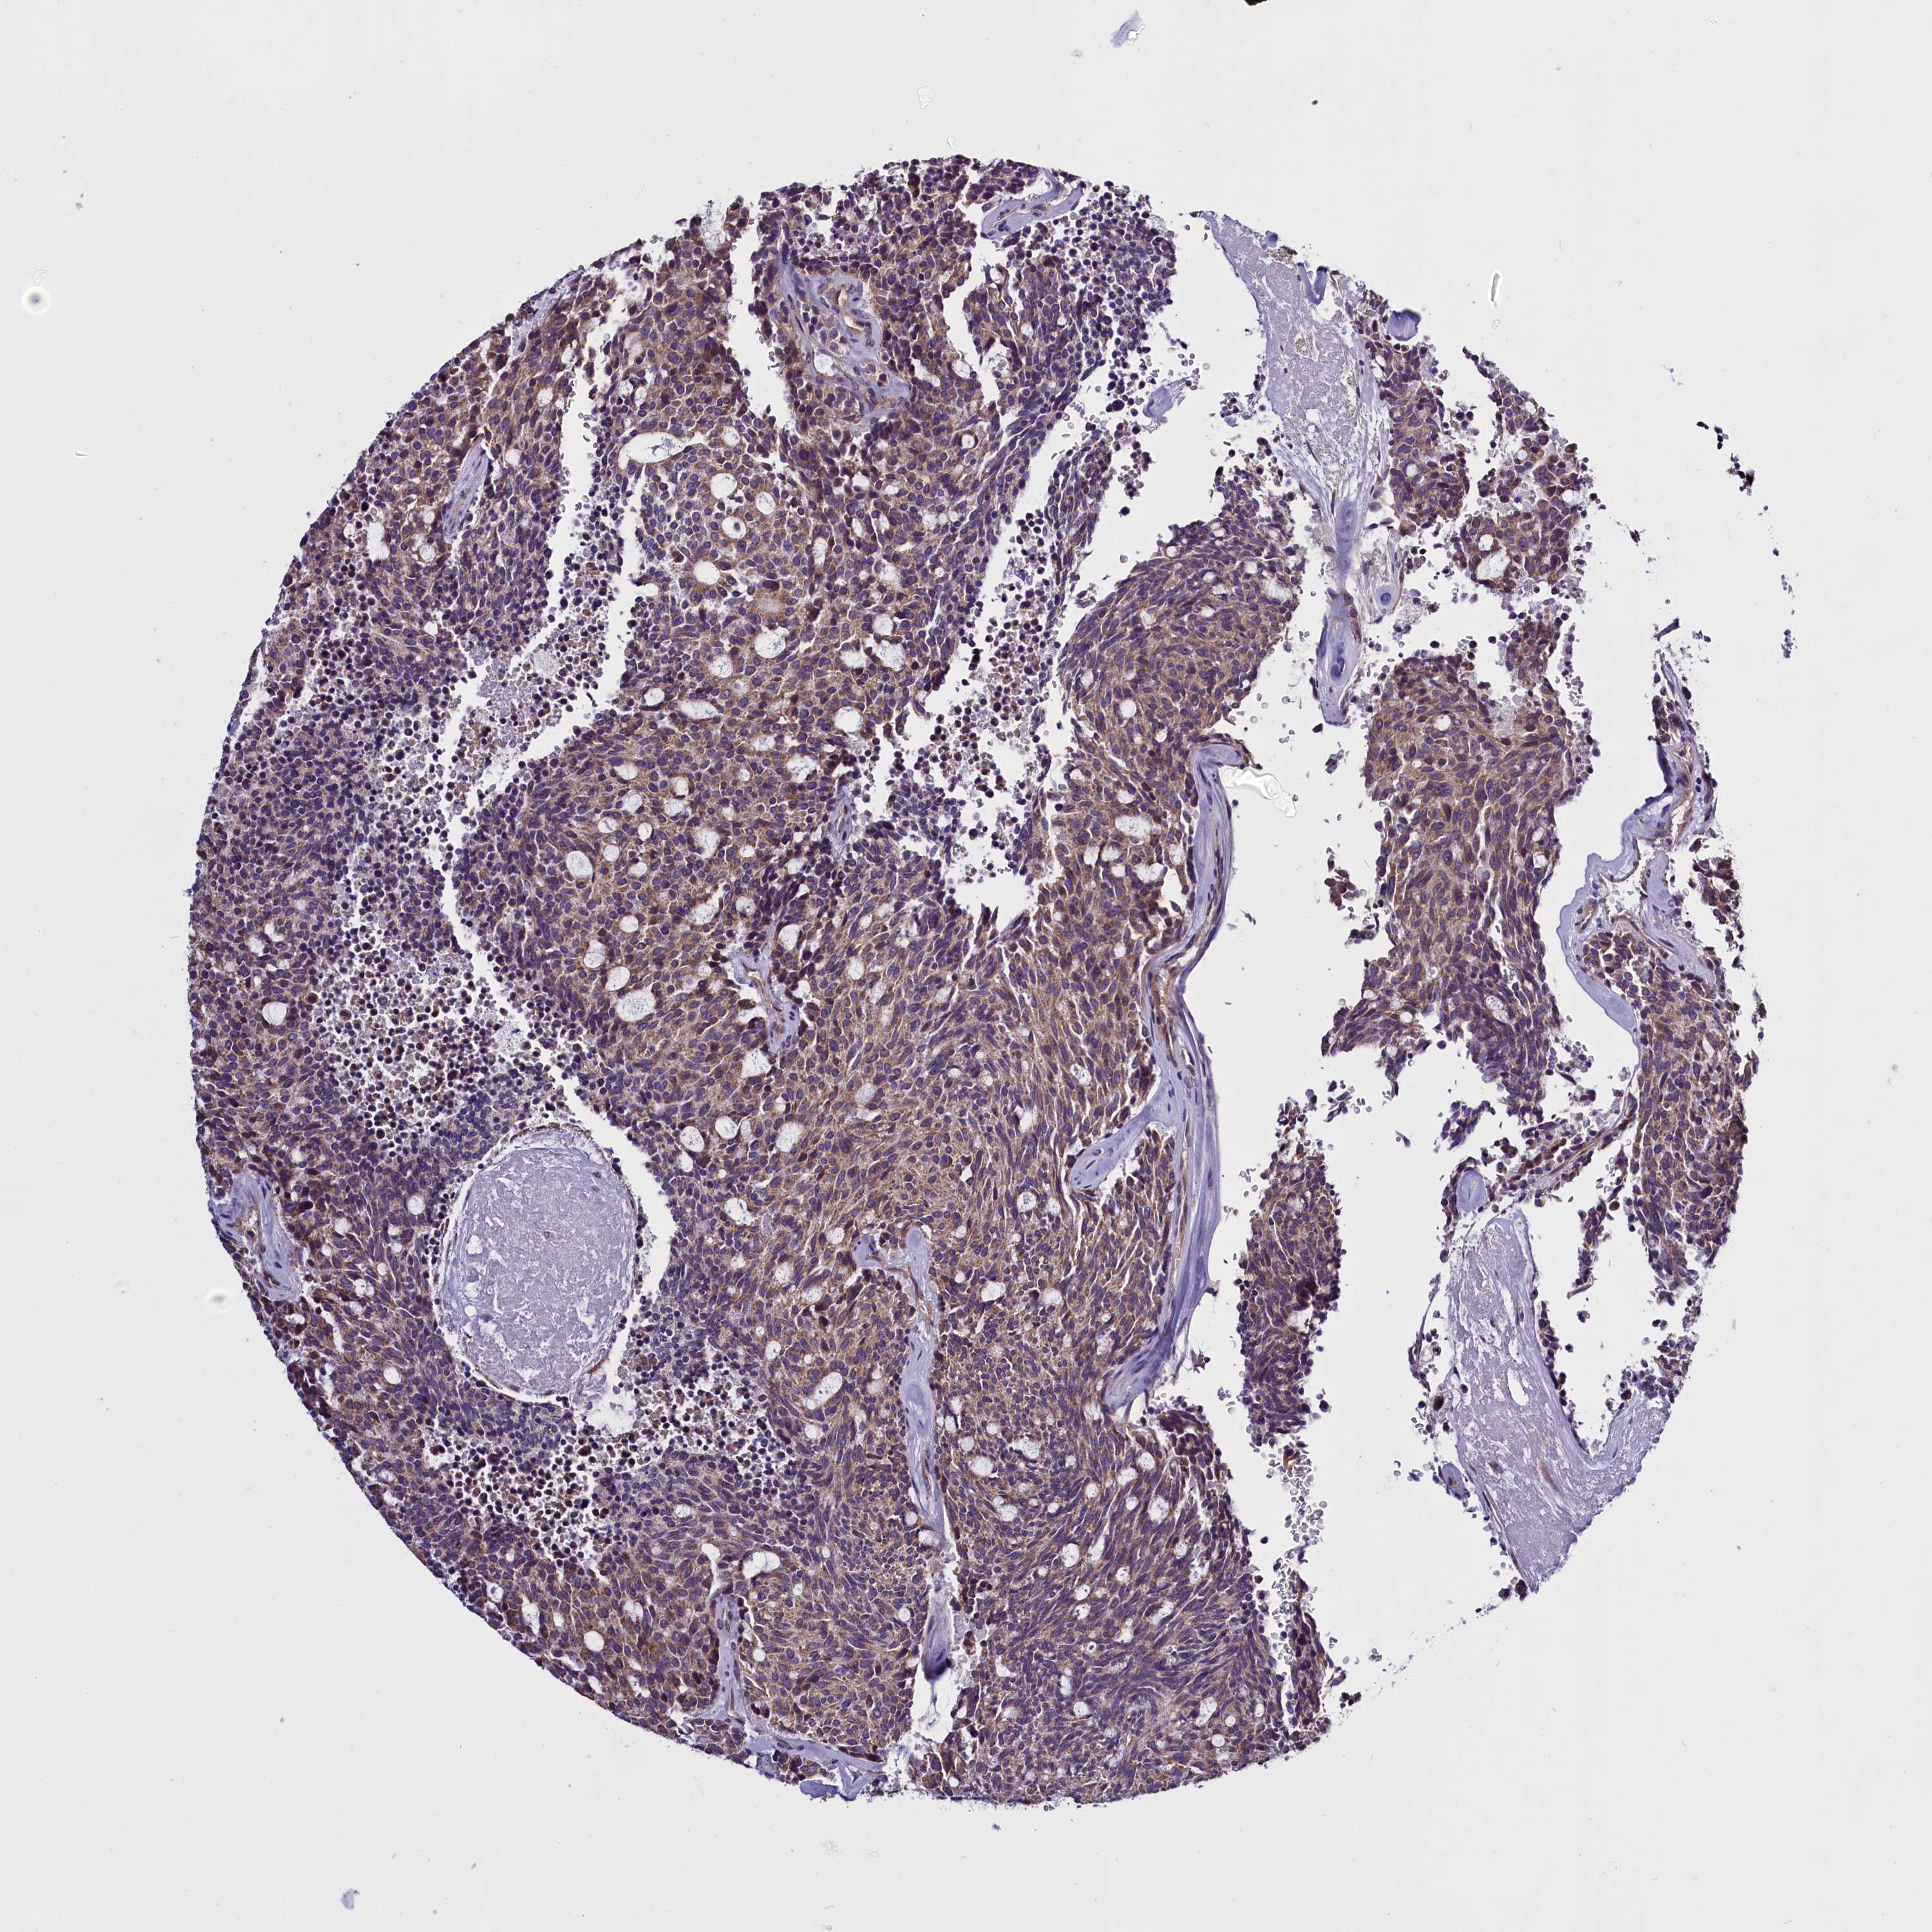

CARCINOID - Protein expressioni

A mouse-over function shows sample information and annotation data. Click on an image to view it in a full screen mode. Samples can be filtered based on level of antibody staining by selecting one or several of the following categories: high, medium, low and not detected. The assay and annotation is described here.

Antibody stainingi

Antibody staining in the annotated cell types in the current human tissue is reported as not detected, low, medium, or high, based on conventional immunohistochemistry profiling in selected tissues. This score is based on the combination of the staining intensity and fraction of stained cells.

Each image is clickable and will lead to virtual microscopy that enables deeper exploration of all samples and also displays staining intensity scores, fraction scores and subcellular localization as well as patient and tissue information for each sample.

Antibody HPA041412

Antibody HPA056006

Staining

High

Medium

Low

Not detected

Intensity

Strong

Moderate

Weak

Negative

Quantity

>75%

75%-25%

<25%

None

Location

Nuclear

Cytoplasmic/membranous

Cytoplasmic/membranous,nuclear

Carcinoid, malignant, NOS

Carcinoma, NOS